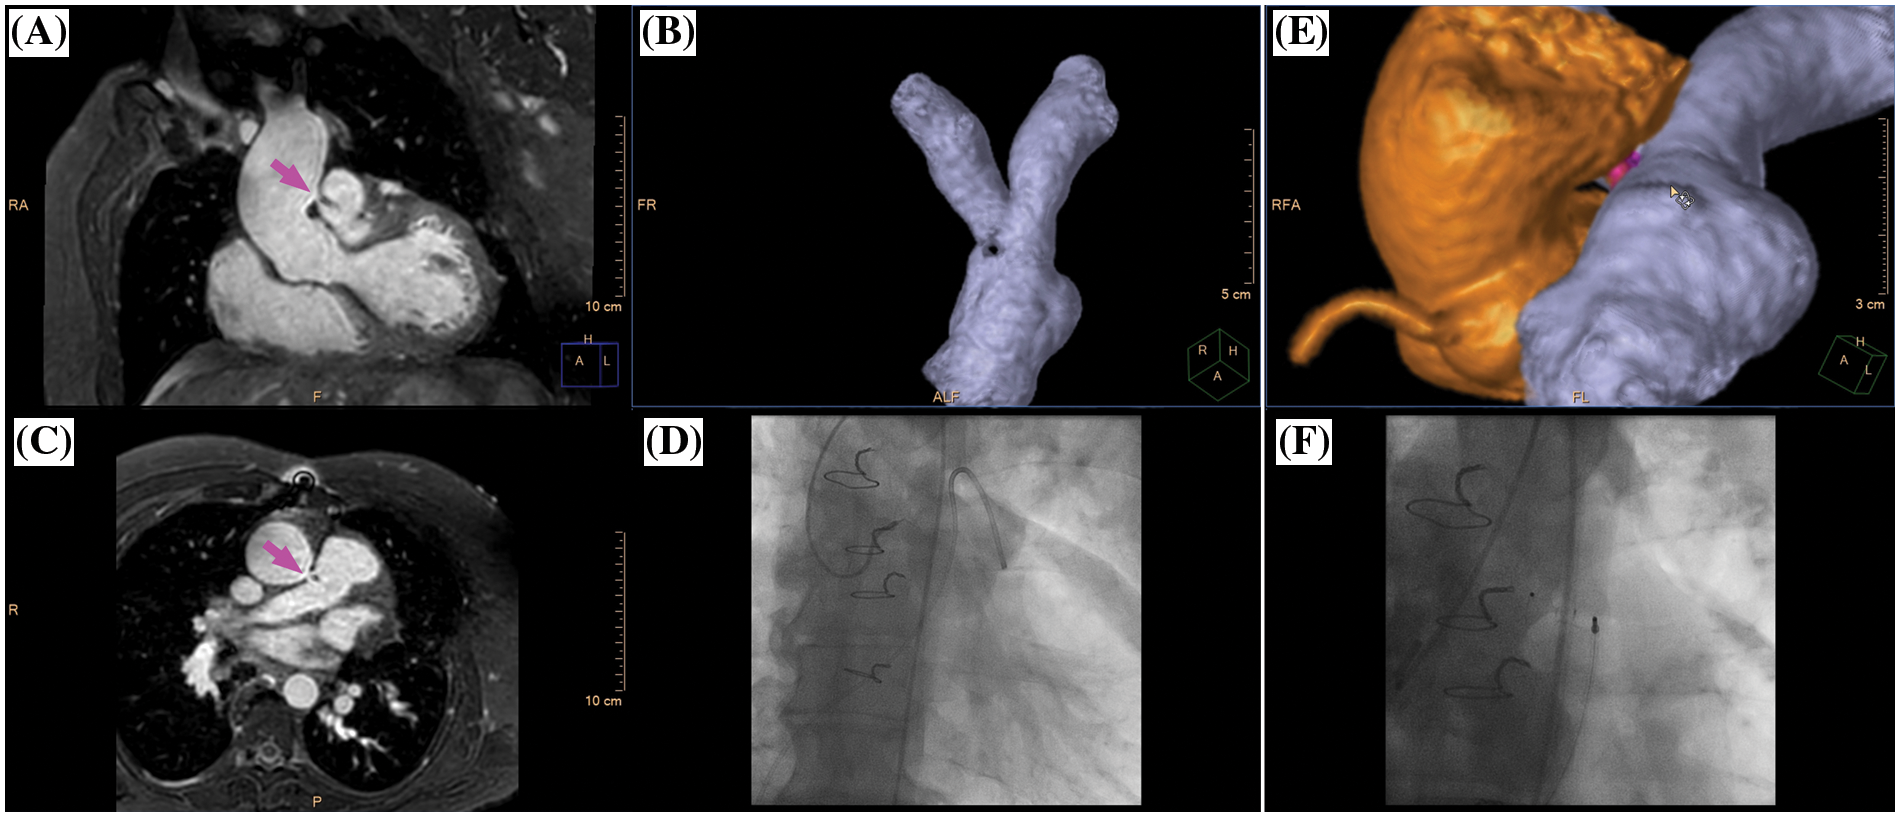

CMR imaging is often requested prior to interventional or surgical treatment when three-dimensional segmentation of the cardiac and vascular cavities is needed for preprocedural planning and peri-procedural guidance [5,17]. Especially in patients with congenital heart disease, detailed anatomical assessment of all cardiac and vascular structures is crucial for therapeutical decision making and interventional assistance (Figs. 3–5, Video S1–S3). At present, contrast-enhanced 3D dynamic MR angiography represents the widely accepted standard for the evaluation of the thoracic vessels in children [2]. However, the timing of image acquisition needs to be designed for the clinical question and depiction of vascular structures is invariably limited to the targeted circulation. The present study corroborated a significant SIR decrease together with a limited anatomical assessability of vascular structures in the non-targeted circulation for conventional 3D MR angiography. When aiming at the anatomical assessment of both, the pulmonary and systemic circulation, 4D MR angiography could be used instead. The most important benefit of the 4D technique relies on the inherent temporal resolution, enabling the assessment of dynamic flow conditions in the observed vascular region. However, the present study data showed that the advantage of a time-resolved MR angiography went at the expense of an overall reduced SIR when compared to 3D angiography which confirmed former study data reporting a decreased image quality of 4D angiography [18]. An additional disadvantage of contrast-enhanced dynamic MR angiography for evaluation of CHD patients relates to the usually ECG untriggered acquisition being designed for extracardiac vessel depiction and, thus, being less suitable for intracardiac morphology evaluation [19].

Figure 3: Clinical case example I. (A) Volume-intensity projection; (B) volumetric surface rendering; (C) angulated volume-intensity projection for depiction of fenestration site (right anterior oblique angulated view, magenta arrow); D1 and D2, composite volumetric surface rendering of vascular compartments/endoluminal cavities including intracardiac lateral tunnel (blue), fenestration (magenta), atria (transparent green), coronary sinus (yellow) and single ventricle (red). Please refer to video 1 for a fully animated case presentation

Figure 4: Clinical case example II. (A) Multiplanar-reformatted projectional view of nsWHcs for depiction of the aortopulmonary window (coronal geometry, magenta arrow); (B) volumetric-surface rendering of main pulmonary artery bifurcation with clear demarcation of an intraluminal signal loss resulting from jet-related flow disturbances; (C) multiplanar-reformatted projectional view in transversal geometry at the height of the aortopulmonary window (magenta arrow); (D) X-ray fluoroscopy with semi-selective contrast injection of aortopulmonary window and subsequent pulmonary arterial enhancement; (E) volumetric surface rendering of nsWHcs for 3D display of aortic root/ascending aorta (orange), aortopulmonary window (magenta) and main pulmonary artery/pulmonary arterial bifurcation site (blue); (F) X-ray fluoroscopic angiography of thoracic aorta following occluder implantation of aortopulmonary window. Please refer to video 2 for a fully animated case presentation

Clinical case example I (same case as shown in Fig. 3)

Three-dimensional whole heart imaging using nonselective balanced SSFP with compressed SENSE (nsWHcs) in an 11-year-old boy (bodyweight, 20 kg; heart rate, 65/min; propofol sedation) with a single ventricle and total cavopulmonary connection with intracardiac lateral tunnel prior to radiofrequency ablation of ectopic atrial tachycardia. Note the flow-independent homogeneous blood pool signal in all vascular compartments/endoluminal cavities resulting in clear depiction of the fenestration site of the intracardiac lateral tunnel which is crucial for guidance of atrial catheter access.

Video 2 (.MP4 file)

Clinical case example II (same case as shown in Fig. 4)

A 48-year-old male (bodyweight, 82 kg; heart rate 65/min; diazepam sedation) with prior surgical ventricular septal defect (VSD) closure in early childhood presented with progressive pulmonary hypertension and new-onset atrial flutter raising suspicion of residual VSD. CMR imaging identified extracardiac shunting from an aortopulmonary window (luminal diameter 7 mm) located about 25 mm cranial of the left coronary cusp of the aortic valve with continuous systolic-diastolic jet-related flow disturbances. Percutaneous occluder implantation was successfully performed.